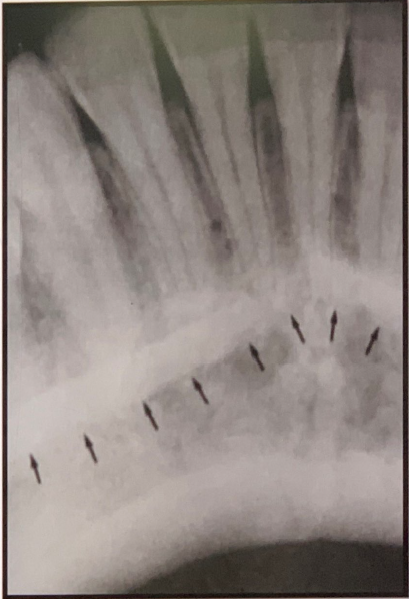

83. what does arrow show?

Hamular notch

• Shape: Narrow, curved radiolucent depression. • Location: Just behind the last maxillary molar (maxillary tuberosity), extending toward the pterygoid plates. • Medially: Ends at or near the hamulus, which appears as a small, pointed radiopaque structure.